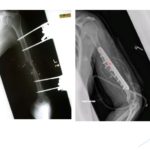

Trans Olecranon Fracture Dislocations

Courtesy: Georgios Arealis, FRCSOrth, PhD